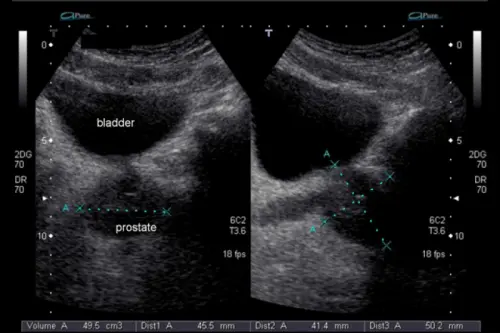

В клініці Астрамедіка УЗД простати проводиться трансабдомінальним методом (через передню черевну стінку) на ультразвуковому сканері експертного класу Mindray Resona I8. Цей метод чудово підходить для первинної діагностики та скринінгу захворювань простати. Апарат оснащений революційною технологією ZONE Sonography, яка забезпечує більш чітке зображення порівняно з традиційними системами. Технологія ZST+ дозволяє досягти високої просторової та часової роздільної здатності, що критично важливо для точної оцінки структури передміхурової залози.

На екрані ультразвукового сканера Mindray Resona I8 в реальному часі видна структура простати, сечового міхура та навколишніх тканин. Завдяки технології ZONE Sonography зображення виходить чітким та деталізованим, що дозволяє лікарю точно оцінити стан передміхурової залози. Лікар робить заміри в кількох проекціях (поздовжній та поперечній), оцінює симетрію часток простати, чіткість контурів, однорідність структури тканин, вимірює об'єм залози. Додатково вимірюється об'єм залишкової сечі в сечовому міхурі — пацієнта просять помочитися, після чого проводиться повторне сканування для оцінки цього важливого показника.

Будь-які відхилення від норми — збільшення розмірів, неоднорідність структури, ділянки підвищеної або зниженої щільності, кісти, кальцинати — докладно описуються в протоколі дослідження. Розшифровка УЗД простати видається одразу після процедури на руки пацієнту, а при виявленні патологічних змін лікар рекомендує консультацію уролога для призначення лікування.

Норми УЗД простати залежать від віку чоловіка. У молодих чоловіків 20-40 років об'єм передміхурової залози зазвичай становить 20-25 см³, розміри: довжина 2,5-3,5 см, ширина 2,5-4 см, товщина 1,5-2,5 см. Після 50 років допустиме збільшення до 30 см³ за рахунок вікових змін. Структура повинна бути однорідною, середньої ехогенності, контури рівні та чіткі, сім'яні пухирці симетричні, без розширень.

Аденома простати на УЗД проявляється збільшенням об'єму залози (більше 30-40 см³), появою вузлових утворень, деформацією контурів. Часто страждає середня частка, яка виступає в просвіт сечового міхура, що добре видно при трансабдомінальному дослідженні. При аденомі важливо оцінити кількість залишкової сечі — якщо вона перевищує 100 мл, це свідчить про виражене порушення відтоку і вимагає активного лікування. Кісти простати виглядають як округлі анехогенні (темні) утворення з чіткими контурами, вони можуть бути вродженими або набутими на тлі хронічного запалення.